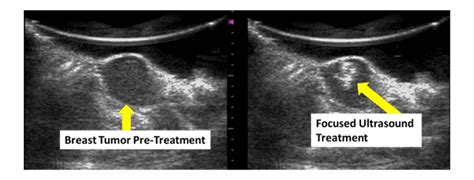

Breast ultrasound uses sound waves to make a computer picture of the inside of the breast. On ultrasound, a breast cancer tumor is often seen as hypoechoic, has irregular borders, and may appear spiculated. On ultrasound it will be hypoechoic with spiculations radiating away from the nipple. You might not need any further tests if everything looks normal. A specialist looks at the ultrasound pictures. However, in rare cases, breast cancer can be the cause of gynecomastia so, a full mammographic. Mammogram imaging may show skin thickening, but often there is no distinct mass found on physical examination or … Both malignant and benign lesions may show either circumscribed or poorly defined margins. Notice that there is some fibroglandular tissue on the right, while on the left there is only subcutaneous fat. If a solid lump shows on the scan you might need to have. There is a higher incidence in people from china and africa due to hyperestrogenism secondary to parasitic liver disease. 17 years experience general surgery. This breast cancer ultrasound image shows changes related to breast cancer that are not seen as microcalcifications or a mass or lump.

On ultrasound it will be hypoechoic with spiculations radiating away from the nipple. Rapid onset of symptoms (redness, swelling, warmth, itching, skin thickening) are hallmarks of the disease. 17 years experience general surgery. Mass due to cancer on ultrasound, a breast cancer tumor is often seen as hypoechoic, has irregular borders, and may appear spiculated. Is the abnormal enlargement of rudimentary male breast tissue. You may have an imaging test, like a mammogram or ultrasound, for an inside look. This breast cancer ultrasound image shows changes related to breast cancer that are not seen as microcalcifications or a mass or lump. This test is often used when a change has been. Other ultrasound findings that suggest breast cancer include: Malignant disease in men just looks like malignant disease in women. A specialist looks at the ultrasound pictures. Dcis on mri may create an area of irregular enhancement of the mri dye into the breast. On the flip side, there are benign (not cancerous) breast changes which can mimic breast cancer as well.

The Radiology Assistant : Pathology of the Male Breast from rad.desk.nl Below are images of dcis on breast ultrasound. Other ultrasound findings that suggest breast cancer include: This breast cancer ultrasound image shows changes related to breast cancer that are not seen as microcalcifications or a mass or lump. A doctor may order a breast ultrasound if a physical exam or. You may get a biopsy. The exact cause of breast. Breast cancer is among the most common causes of cancer deaths today, coming fifth after lung, stomach, liver and colon cancers. Both malignant and benign lesions may show either circumscribed or poorly defined margins.